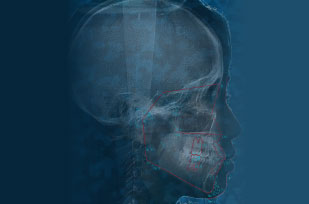

骨格や歯の位置・噛み合わせなどがわかるセファロ撮影に、分析ソフトを併用して治療前後を比較・成長を予測。